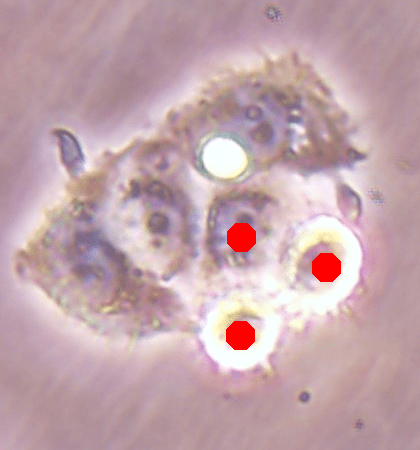

![]() |

| (a) | (b) |

| (c) | (d) |

For an example subimage given in Fig. 2a, these distance definitions are illustrated in Figs. 2b and 2c, respectively. The inner distance definition well indicates the cell centers since it uses the Euclidean distances from pixels to their closest cell centers. However, as it uses the centers as the reference point, the distance decrease from a center to its boundaries is the same for all directions and for all cells. Thus, when it is used alone, this definition imposes a circular and one-sized shape on the cells, as also seen in Fig. 2b. On the contrary, since the normalized outer distance is calculated with a reference to a cell boundary, this decrease may differ from one direction to another as well as from one cell to another, depending on the shape and size of the cell. Thus, it better preserves the morphological characteristics of cells, as seen in Fig. 2c.

The proposed DeepDistance model considers cell detection as a multi-task regression problem that estimates two distance maps from the RGB image, one for formulating the main task of cell detection and the other as an auxiliary task with the motivation of more effectively learning the main task. The FCN architecture given in the previous section is designed to learn these two regression tasks at the same time. This section discusses how this model can be extended to cover more auxiliary tasks, concurrent learning of which may further increase the performance of the main task. For this purpose, this section implements an extended version of the DeepDistance model that comprises an additional task of cell pixel classification. This additional task aims to construct a classification map (as shown in Fig. 2d) from the shared features of the encoder path111To take overlapping cells apart, and hence to obtain an improved map, cell boundaries are widen and subtracted from the classification map. This improved map is also used in the comparison methods to make fair comparisons.. Note that here, instead of defining another regression problem as the additional task, we use a classification problem in order to demonstrate that the model can easily be extended to cover the auxiliary tasks related with regression as well as classification.